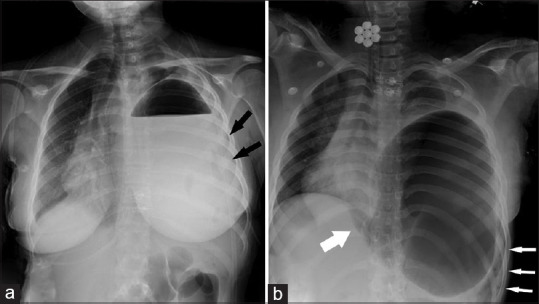

The presence of the stomach in the thorax is called gastrothorax. If excessive dilatation occurs due to a valve mechanism in the stomach which then is herniated into the thorax, it is called tension gastrothorax and the situation can be life-threatening. In late presentation, congenital diaphragmatic hernias or traumatic diaphragmatic hernias, if the stomach located in the thorax is severely distended, it can be confused with tension pneumothorax or pleural effusion/empyema. We presented tension gastrothorax in two patients with distended stomach in the thorax, in which tension pneumothorax and pleural effusion/empyema-like images were created, based on plain X-rays taken at the first admission in the emergency department, which may cause diagnostic confusion. The tension gastrothorax can cause mediastinal shift, which can lead to respiratory distress and eventually cardiac arrest secondary to obstructive shock. In case of mediastinal shift, it should reduce the tension of the stomach located in the thorax by inserting a nasogastric catheter, and if this fails, by aspiration with a needle.